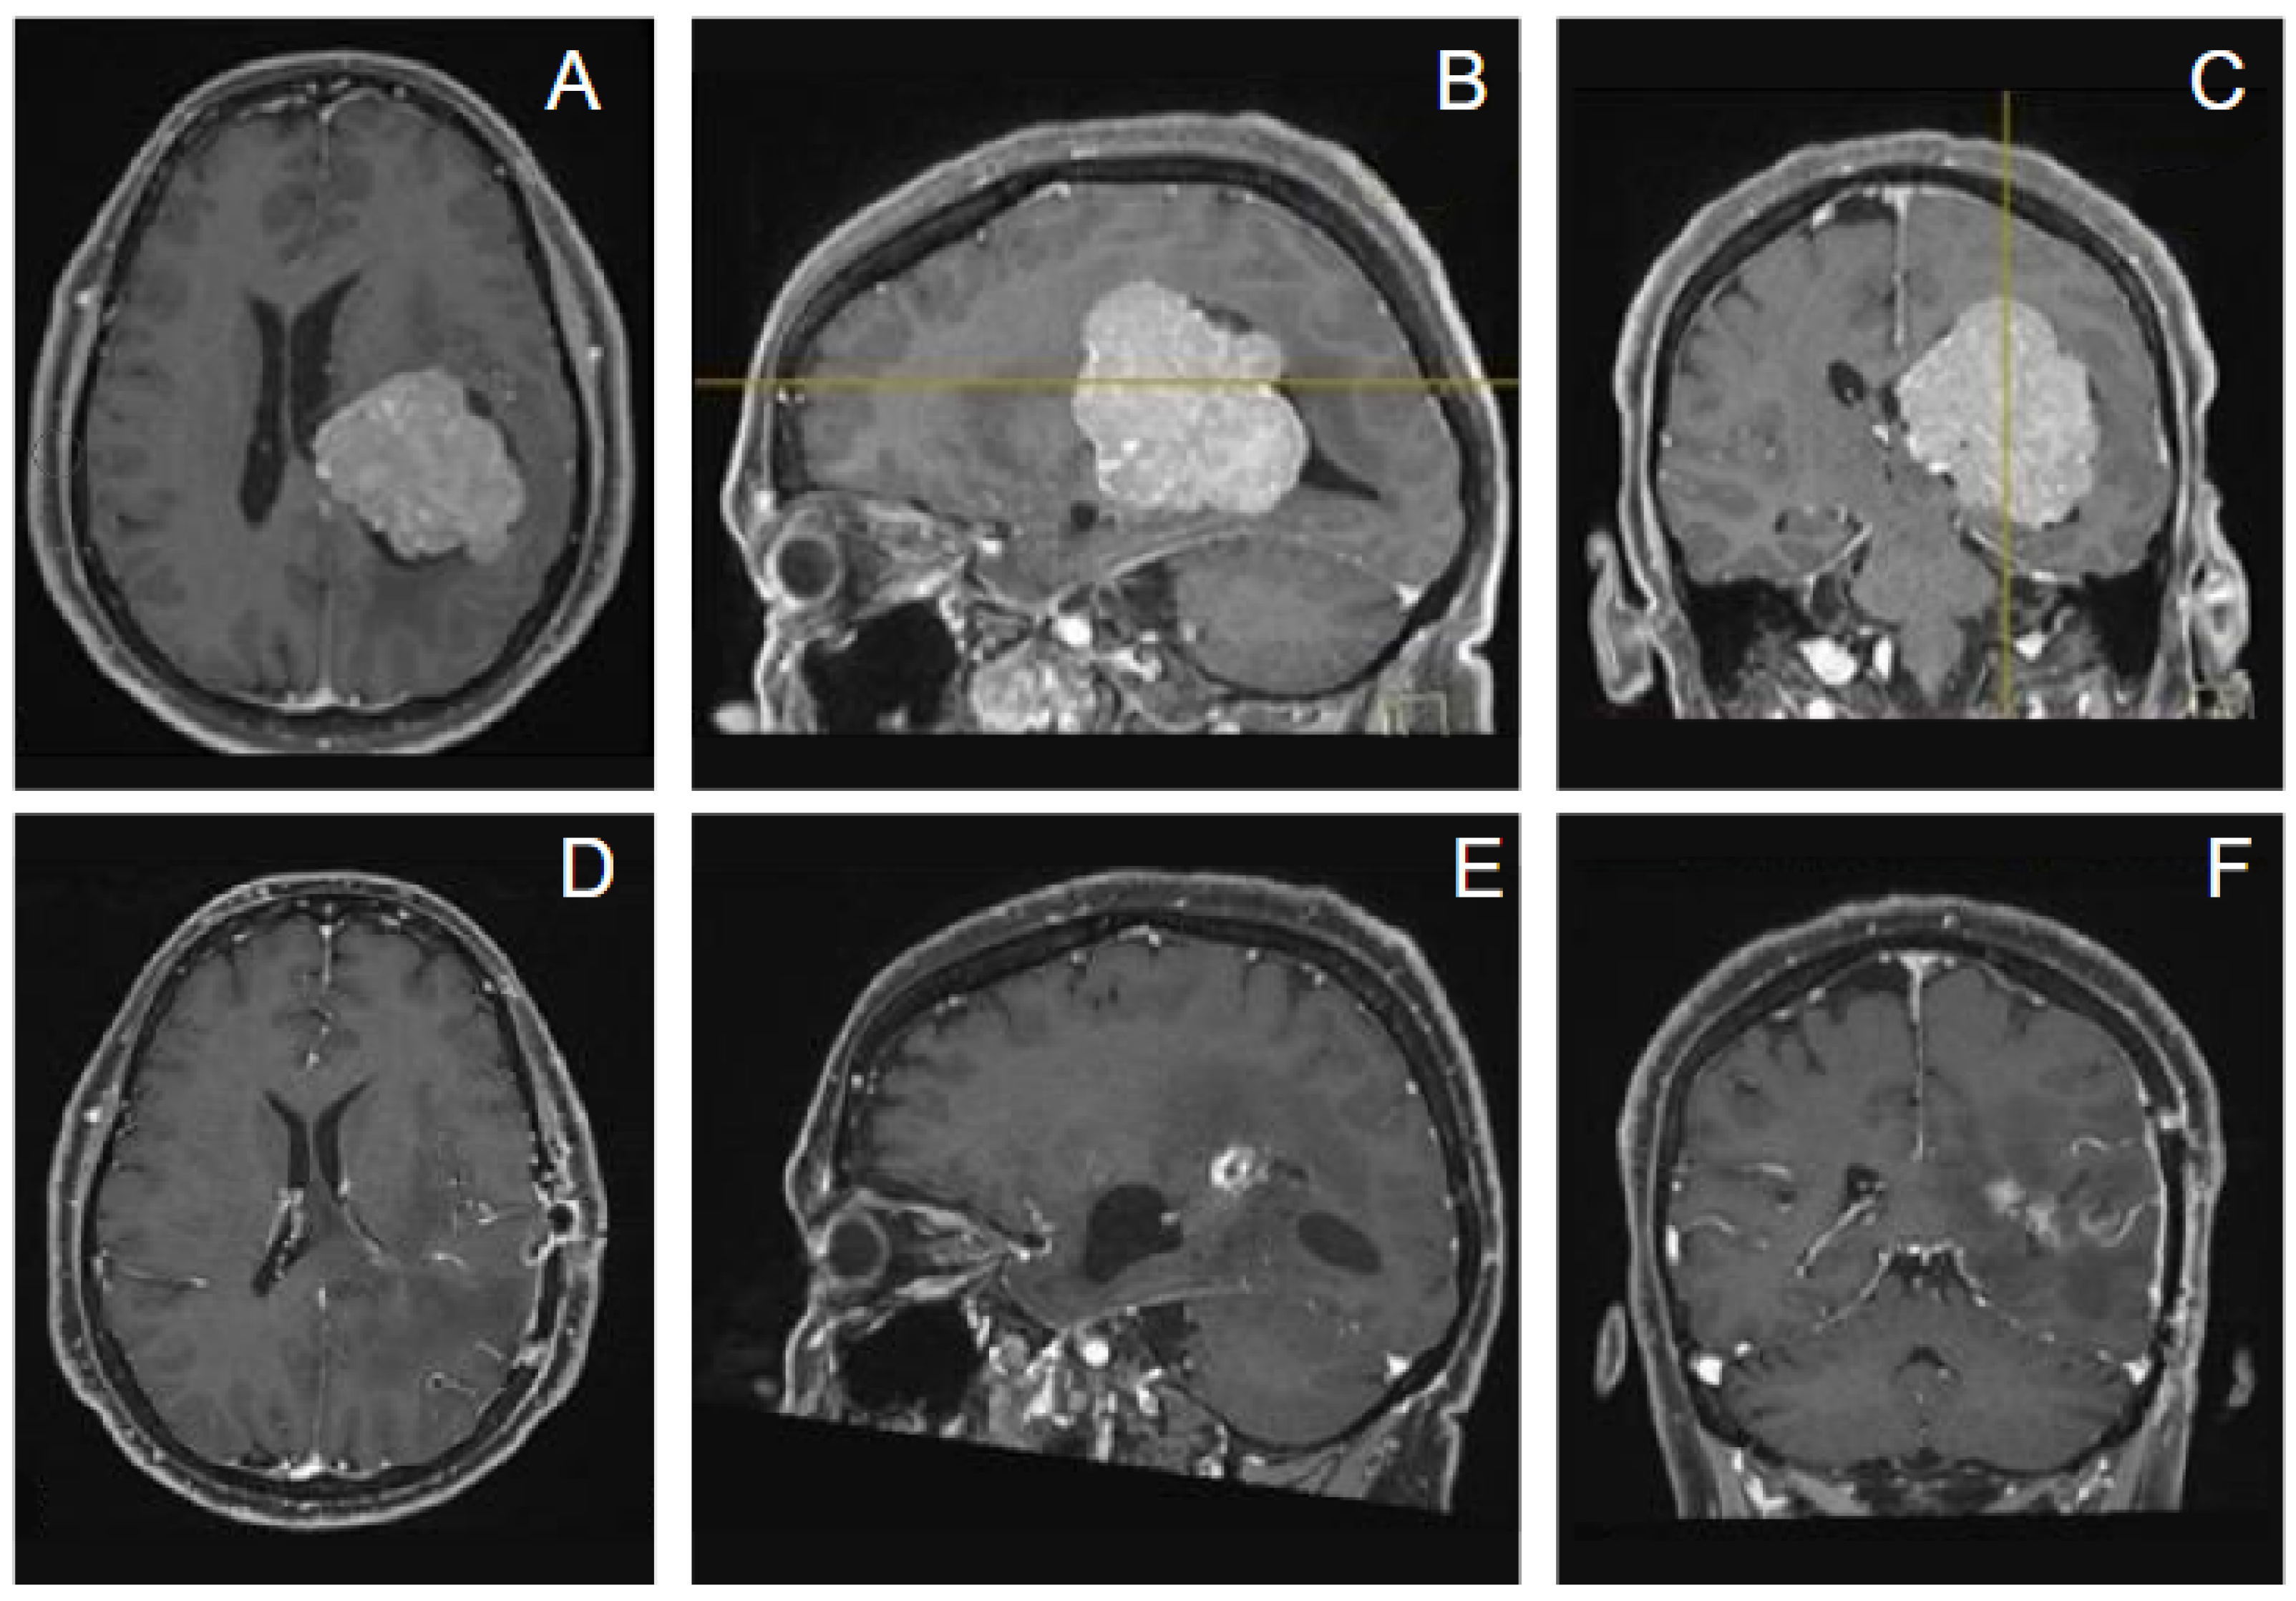

- Case 2. A 56-year-old woman presented with memory impairment; dysarthria and neurological exam revealed hyposthenia at the right limbs. A contrast-enhanced MRI showed a large intraventricular mass in the left trigone with peritrigonal extension consistent with meningioma (Figure 7). We adopted for the patient a lateral position and a trans-sulcal temporal approach with port technique, neuronavigation-assisted. Surgery was uneventful and a gross total resection was obtained. Pathology revealed a WHO grade 2 meningioma. Postoperative MRI confirmed complete resection of the tumor. Adjuvant radiation therapy was not recommended due to complete tumor resection; the patient was neurologically intact and followed up.